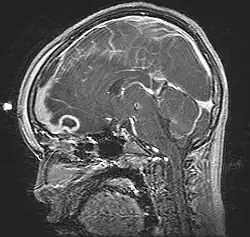

| Pott's puffy tumor, spreading towards person's brain. MRI, T1, sagittal, gadolinium contrast. | |

Pott's puffy tumor, first described by Sir Percivall Pott in 1760, is a rare clinical entity characterized by subperiosteal abscess associated with osteomyelitis. It is characterized by an osteomyelitis of the frontal bone, either direct or through haematogenic spread. This results in a swelling on the forehead, hence the name. The infection can also spread inwards, leading to an intracranial abscess. Pott's puffy tumor can be associated with cortical vein thrombosis, epidural abscess, subdural empyema, and brain abscess.

Although it can affect all ages, it is mostly found among teenagers and adolescents. It is usually seen as a complication of frontal sinusitis or trauma. Medical imaging can be of use in the diagnosis and evaluation of the underlying cause and extent of the condition. Ultrasound is able to identify frontal bone osteomyelitis,[1] while computed tomography (CT) can evaluate bony erosion, and along with magnetic resonance imaging (MRI), can better appreciate the underlying cause and extent of possible intra-cranial extension/involvement.[2][3]